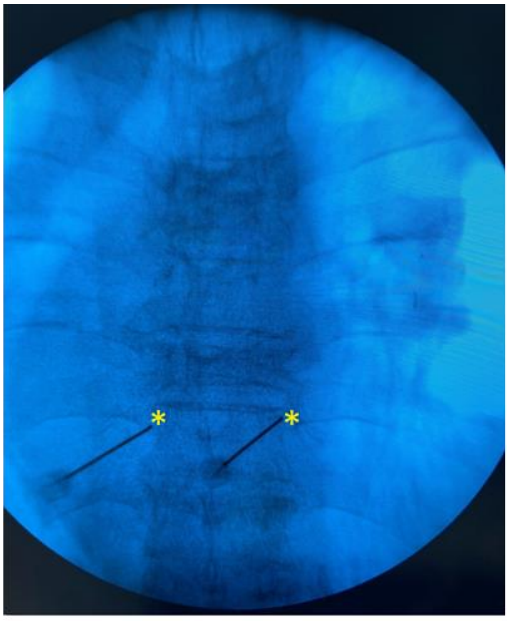

Pre anesthestic checkup was done and consent taken before the procedure. Patient was positioned in the prone position with a pillow underneath the chest and arm by the side. Standard anesthesia monitors were applied. Fluoroscopy was used to identify the right level, counting up from the 12th vertebral body. Target was the supero-lateral aspect of the Transverse process of the vertebra, for the radiofrequency ablation of the medial branches. Adequate caudal and contralateral oblique tilt was given to position the fluoroscope beam parallel to the targeted nerve. 20 G, 10 cm RF cannula ,10 mm curved tip (Boston scientific, USA), were advanced to the target sites in a parallel manner after anesthetizing the skin by lidocaine 2%. (Fig 2) Another two RF cannuale were inserted at T8 and T9 levels in a similar fashion. True lateral views were taken to ensure proper depth of all needles (Fig. 3). The stylets were withdrawn and radiofrequency probes were inserted. At all levels, sensory stimulation at 0.5 V, 50Hz and motor stimulation at 2 Hz up to 1.5 V/2V were obtained.  After Iv sedation, two Radio-frequency lesions were done at 80 degrees Celsius for 90 seconds 2mm apart. 10 mg of methylprednisolone in 1ml lidocaine 2% was injected ta each level to prevent post-ablation neuritis. The same procedure was repeated at the same levels on the other side.

Fig 3 - Lateral view. Needle depth over the TP